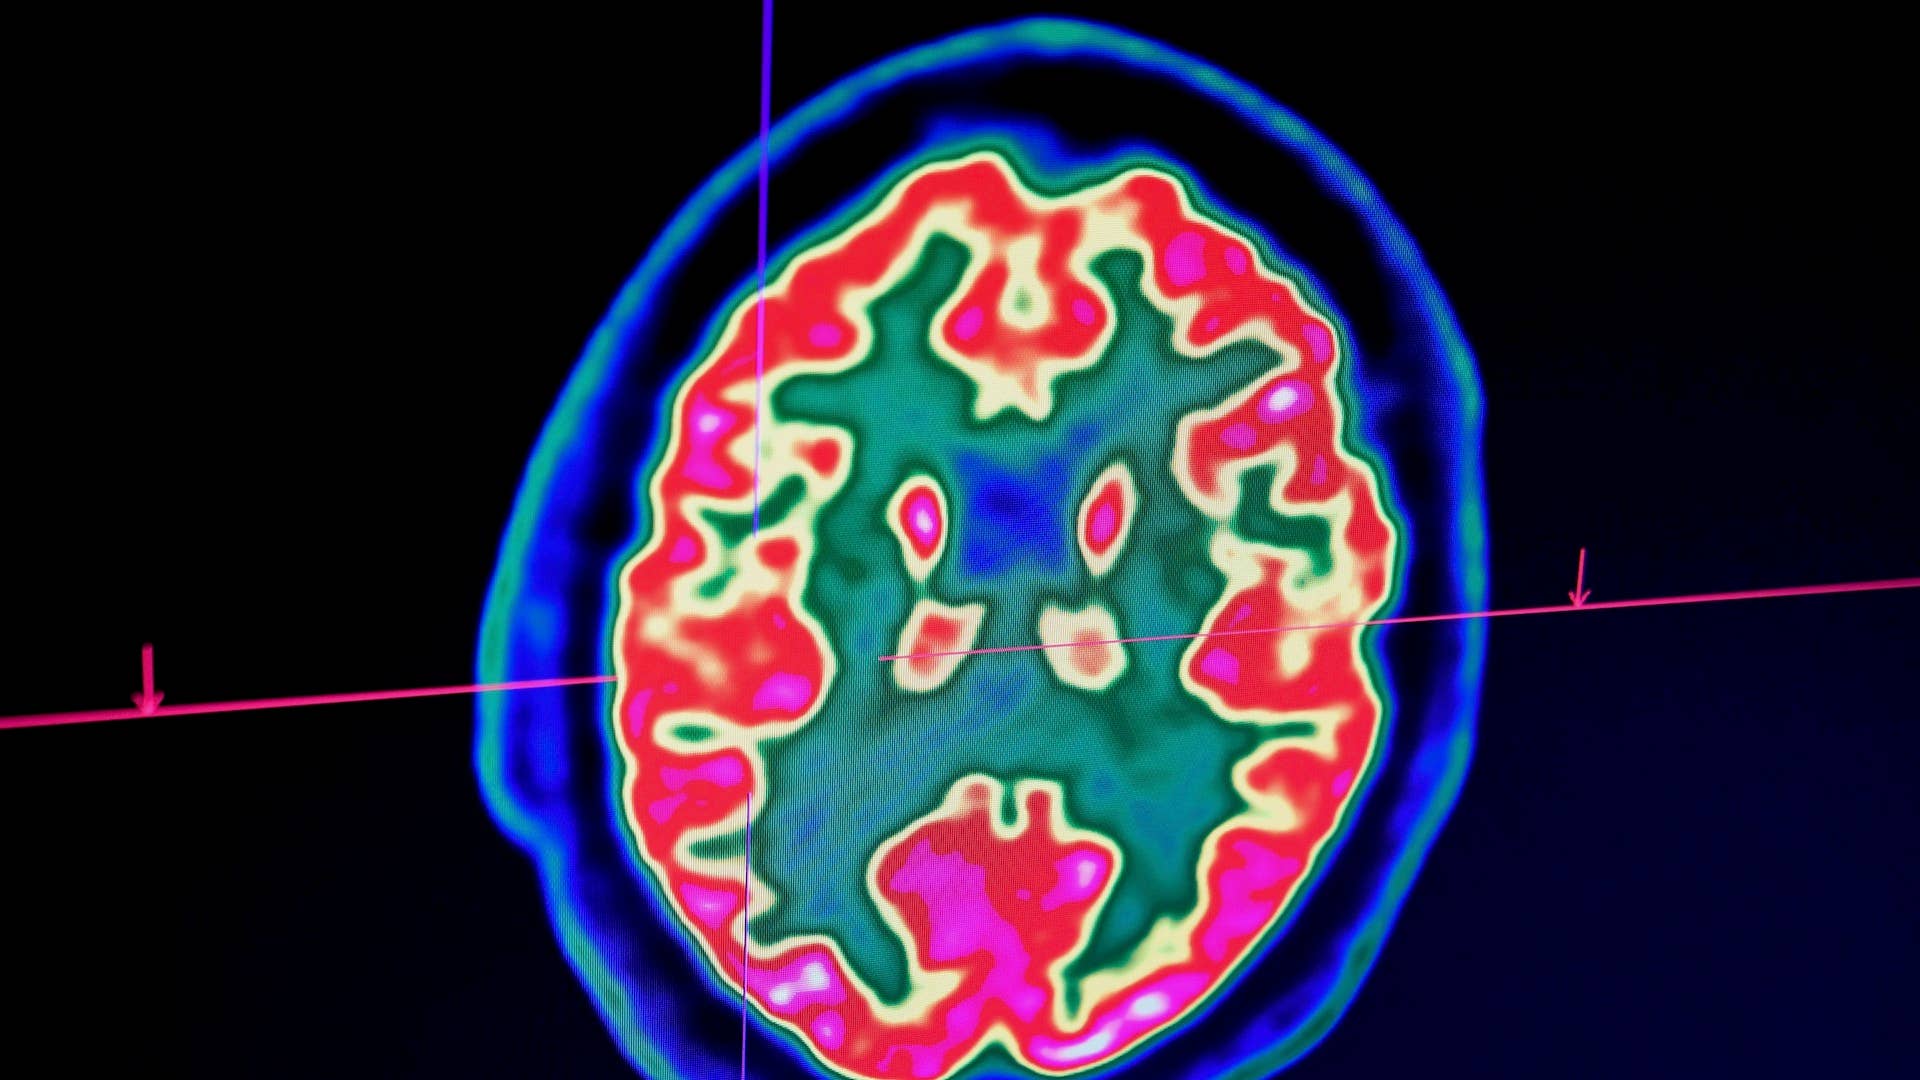

A new study published in Scientific Reports challenges the widespread belief that brain activity comes to a halt immediately at death or shortly after. Researchers at the University of Illinois Chicago found that glial cells not only come alive, but also increase in size and grow arm-like appendages hours after a person dies. Study author Jeffrey Loeb, head of neurology and rehabilitation at the UIC’s College of Medicine, said the findings weren’t “too surprising” as the glial cells are inflammatory “and their job is to clean things up after brain injuries like oxygen deprivation or stroke.”

Researchers analyzed fresh brain tissue from people with neurological disorders and those without. The UIC team discovered that about 80 percent of the analyzed genes didn’t change much during a 24-hour span; but as “the neuronal genes were ramping down,” the so-called “zombie genes” became increasingly active during the first 12 hours after death.